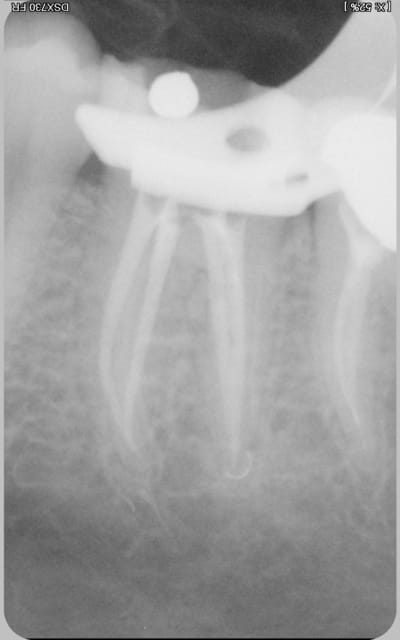

logement canalaire au largo 3, puis machtou vert chauffé au chalumeau.

Radio cône en place avant de le sceller, avec un bon tuck- back et le machtou chauffé au rouge il est rare que le cône reste collé au fouloir. L'avantage de faire la provisoire dans la séance permet de descendre la couronne en plateau et de bien visualiser la chambre pulpaire, particulièrement indiqué dans le cas ci dessus sur des 31 41 d'une personne âgée pulpe rétractée ou à force de la chercher tu trouves .... le desmodonte !))))).